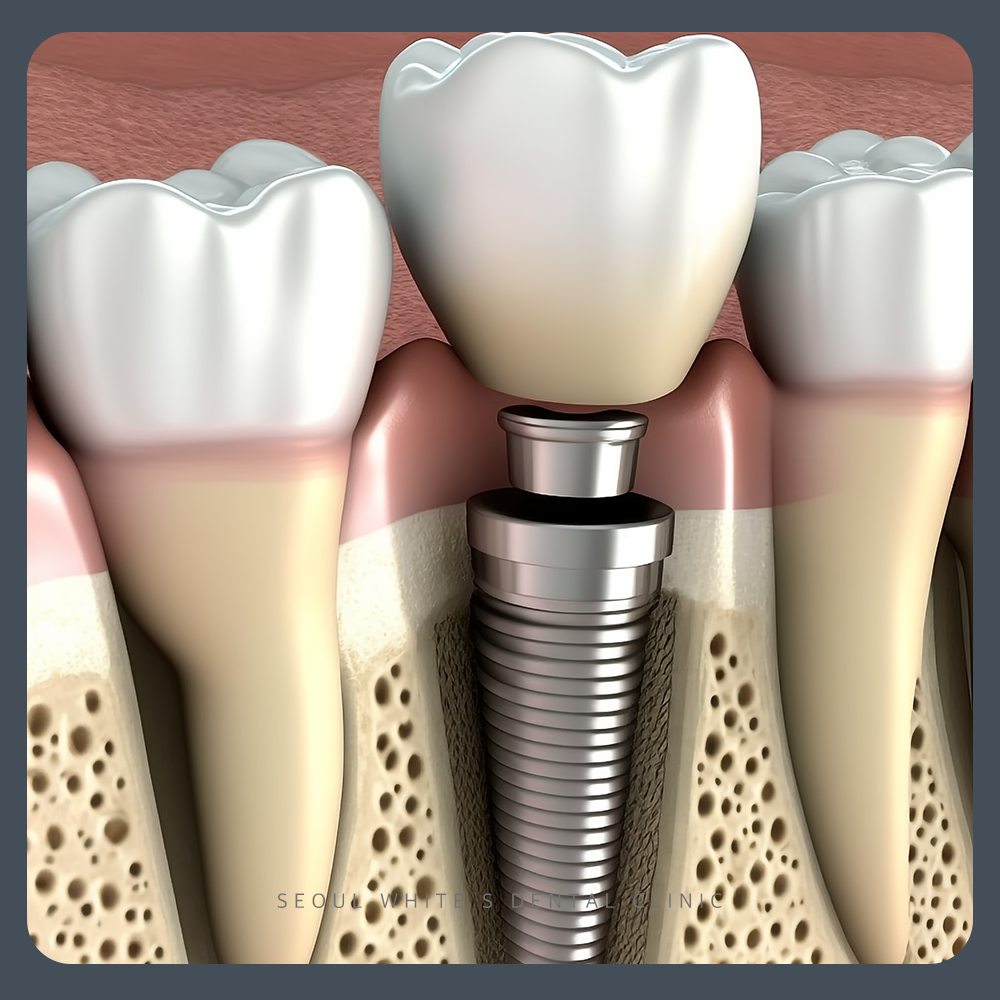

교합(occlusion)이란 입을 다물었을 때, 위아래 치아의 형태학적인 접촉상태와 턱 관절 운동에 의해 닿는 생리적, 운동적 교합 모두를 의미합니다. 따라서 저작이 어려운 분의 치아를 치료할 때, 교합관계를 잘 맞추지 않으면 미세한 접촉 및 접촉이 되지 않는 부분에서 불편함을 느끼실 수 있으므로 매우 중요한 부분이라고 할 수 있어요.

남포동임플란트 서울화이트S치과는 편안한 저작이 가능하실 수 있도록 환자분의 구강 상태를 정확하게 확인 후 치료하며, 환자분께 맞는 교합까지 세심하게 진행해 드리고 있습니다.

남포동임플란트 서울 화이트S치과는 임플란트 사용에 있어 식립 만큼이나 중요한 임플란트 치아보철물에도 가장 적합한 교합상태를 확인하여 제작해드리고 있습니다.